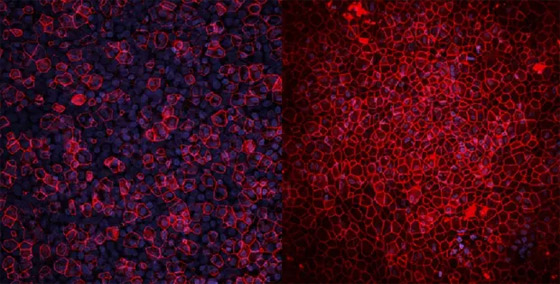

الرئتان اللتان يبلغ عرضهما بضعة ملليمترات فقط، تشبهان رئتي البشر بدرجة طفيفة. وهما موضوعتان في أنبوب بلاستيكي، وعند النظر إلى داخل هذا الأنبوب من أعلى، تبدوان مثل قطعة هلام صغيرة تنتشر في غشاء رقيق. حيث قال شرزانوفسكي: "من الضروري أن نتأكد من نمو الرئتين بما يكفي لتكونا جاهزتين وناضجتين للتجارب، لذلك طوّرنا أقطاباً كهربائية توضع باستمرار فوق نماذج الرئتين، وتراقب الإشارات الكهربية الحيوية لهما".

كما أوضح أنه بناءً على هذه الإشارات "يمكننا أن نتعرف على نضج الرئتين وجاهزيتهما لبدء التجارب. وهذا يشبه توصيل جهاز للمريض ومراقبة دقات قلبه، ولذا فهذا المستشعر الحيوي الذي طوّرناه يساعدنا أيضاً في ملاحظة، مثلاً، متى يكون العلاج فعالاً ومتى تتجدد الرئة المصابة".

أُجريت محاولات أخرى لبناء رئات معملية، لكن شرزانوفسكي يقول إنها بسيطة جداً، وثابتة جداً، لكن رئة الإنسان تتغير وتتوسع وتتحرك باستمرار، بسبب تأثير الدورة الدموية وضربات القلب، على سبيل المثال. الفرق بين هذه النماذج البسيطة والرئتين اللتين صنعهما شرزانوفسكي، صاحب الفكرة، وتلميذته في الدكتوراه ثانه هوين فان، التي أسهمت بدور أساسي في تصميمها وبنائها، هو أنها تتضمن هذه الحركة الفسيولوجية للسوائل في الخلايا.

يقول شرزانوفسكي: "بدأنا في بناء هاتين الرئتين حرفياً خلية خلية، لنجعلها أقرب ما يمكن إلى فسيولوجية رئتي الإنسان. وهذا ما يجعل نموذجنا فريداً من نوعه. والميزة الأخرى لنموذجنا هي أنه يمكننا أخذ خلايا من مرضى مختلفين، وإضافتها إلى هاتين الرئتين لتجربة العلاجات المخصصة".

أضاف: "وميزة أخرى نفتخر بها هي الحجم. فالكثير من النماذج صغيرة جداً، لدرجة أنه لا يمكنك إجراء تجارب كثيرة على نفس النموذج، لكن نموذجنا كبير نسبياً، وهذا يعني أنه يمكننا مراقبة الاستجابات المناعية، والأهداب، وإفراز المخاط، وكل ذلك في نموذج واحد".